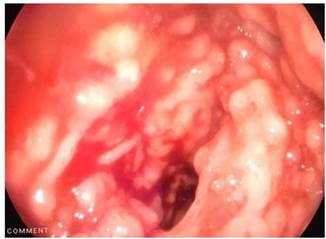

Se trata de un paciente de 15 años de edad, sin antecedentes patológicos previos, que fue remitido a nuestro hospital por hematoquecia. Sus antecedentes familiares son variados: madre diabética tipo 2, tía materna con esclerodermia, tía materna con amiloidosis y bisabuela con cáncer gástrico. Refirió el inicio de enfermedad a los 7 años de edad con cuadro clínico de hematoquecia y dolor abdominal de leve intensidad que mejoraba después de la defecación. En 2011 se realizó una colonoscopía con hallazgos de lesiones sobreelevadas pseudopolipoideas de 3 a 4 milímetros en el colon sigmoide y el recto con una biopsia que reportó malacoplaquia. Recibió tratamiento con ciprofloxacino 500 mg vía oral por 14 días, que mejoró su sintomatología. En 2016 se realizó otra colonoscopia por presentar proctorragia y leve dolor abdominal. Nuevamente se describieron formaciones nodulares pseudopolipoideas en el sigmoides y el recto (Figura 1), con una biopsia que reportó pólipos inflamatorios con focos de agudización, numerosos histiocitos y cambios reactivos del epitelio. En este evento, recibió tratamiento con ciprofloxacino 500 mg vía oral cada 12 horas por 14 días y presentó mejoría de la sintomatología. En julio de 2018, se realizó otra colonoscopia que informó lesiones pseudopolipoideas de distribución irregular con mucosa colónica normal, áreas planas de aspecto nacarado de bordes irregulares (Figura 2), con una biopsia que reportó pólipos inflamatorios, colitis crónica acentuada con tinción de ácido periódico Schiff (PAS), sin encontrar cuerpos de Michaelis-Gutmann.

Figura 2 Lesiones pseudopolipoideas de distribución irregular con mucosa colónica normal, áreas planas de aspecto nacarado de bordes irregulares.

La videocolonoscopia reveló a nivel del colon sigmoide y recto múltiples formaciones pseudopolipoideas sésiles, blandas, ulceradas y hemorrágicas, que medían de 5 a 15 mm de diámetro (Figuras 5 y 6).

Figura 6 Videocolonoscopia a nivel de la mucosa del colon sigmoide y recto en la que se observaron múltiples formaciones pseudopolipoideas sésiles, blandas, ulceradas y hemorrágicas que midieron de 5 a 15 mm de diámetro.